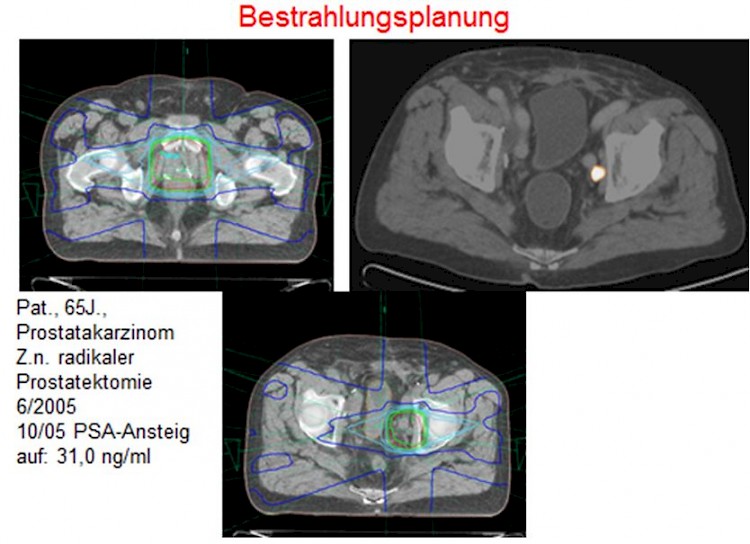

- -FDG eignet sich nicht zur Darstellung von Prostatakarzinomen. Deshalb wird bei der Prostatadiagnostik -Cholin verwendet. Das PET-CT-Verfahren ist beim Re-Staging sinnvoll, da sich bei steigendem PSA-Wert oft fehlende oder unsichere Befunde in der CT ergeben.